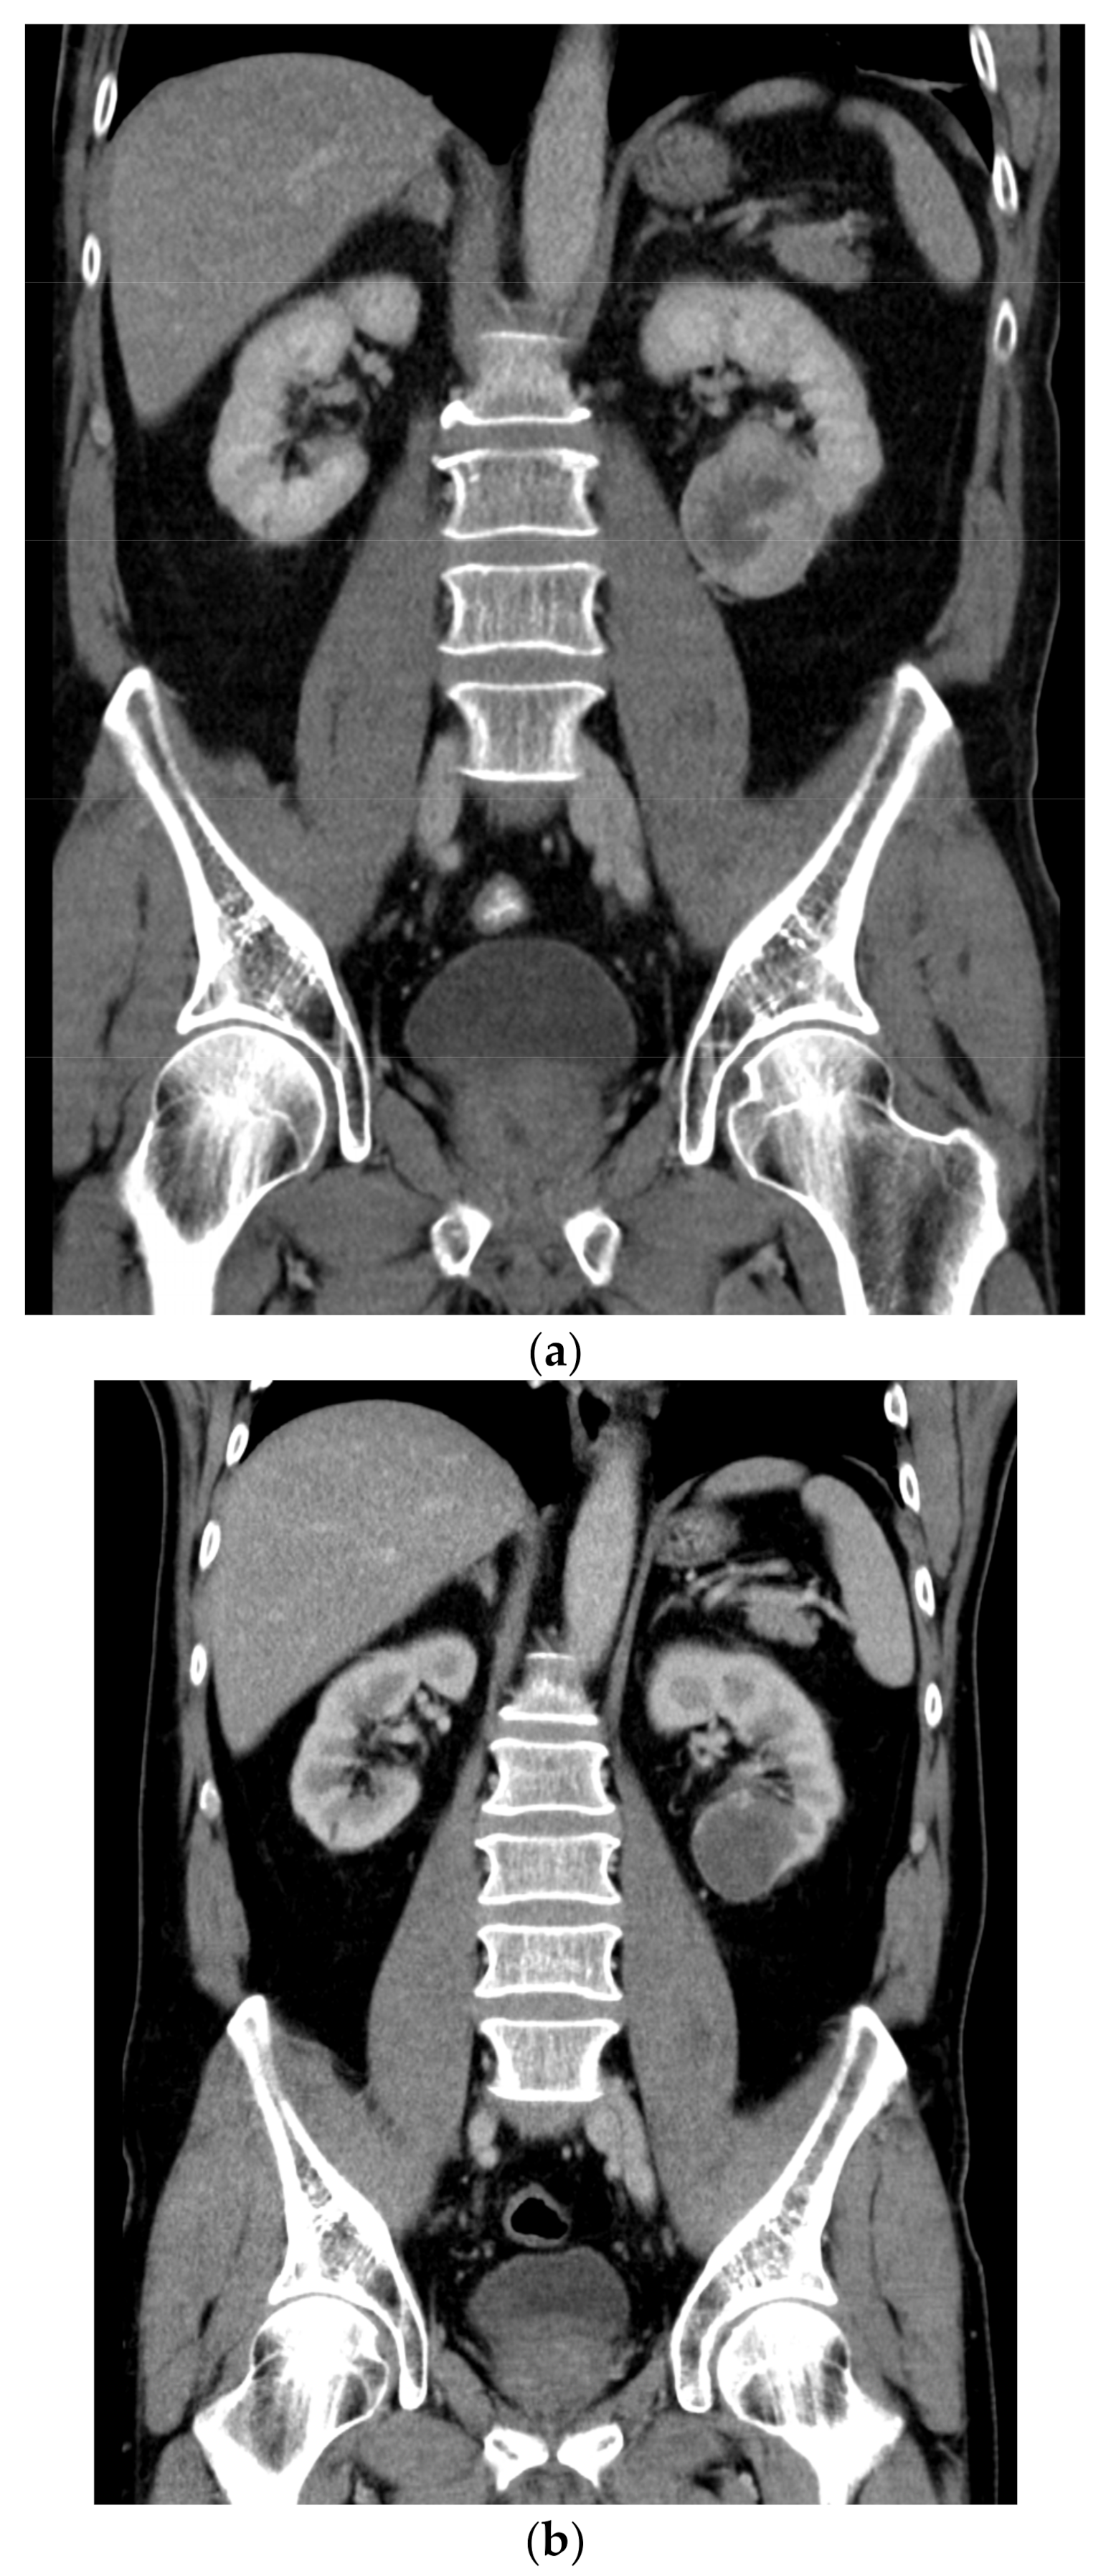

2. Case Presentation